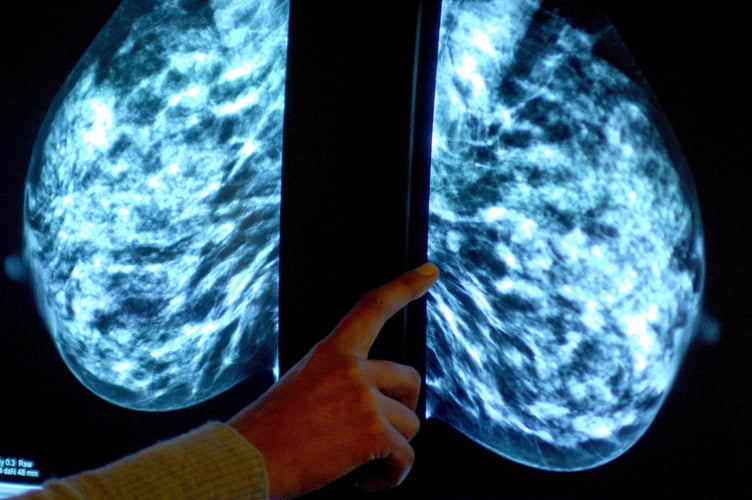

The screening programme sees women aged between 50 and 71 invited every three years to undergo a mammogram (X-ray) designed to detect cancers that are too small to see or feel.